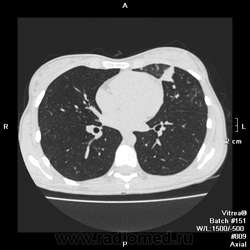

Здравствуйте Уважаемые коллеги! Сделали кт огк девушки 20ти лет, поступала с температурой 38,5, лечат уже вторую неделю, субфебрильная температура, кашель с мокротой. Смущает инфильтрация в S3 левого легкого, пневмония в стадии разрешения?

Да, бронхопневмония в стадии неполного разрешения и фиброза, если смущает, можно протестировать на туберкулез.

Смущали) участки  расположенные вдоль междолевой плевры, округлые очаги

Ну, это как раз признак бронхогенного распределения инфекции.

На 4 скане участки похожие на распад. Проведите анализ мокроты на БК и консультация фтизиатра.